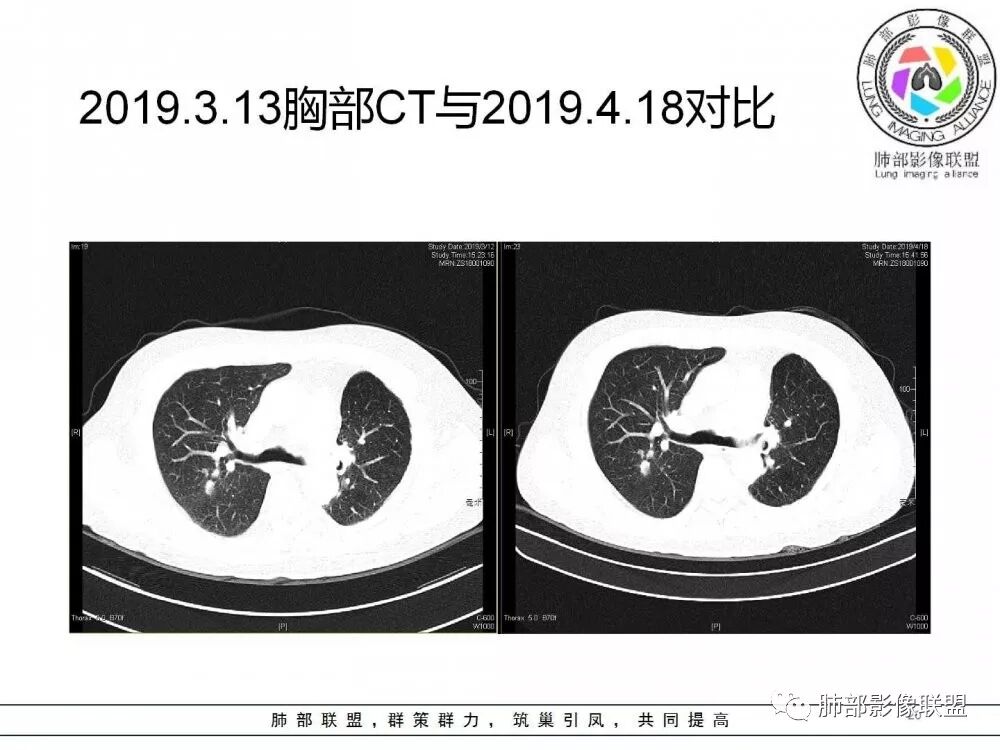

病灶从2月份就开始有,应该最早说是1月7号就有了,到3月13号稍微增大一点,到后面几乎没变化,到5月份好像稍微大一些,炎性应该是炎性,犹豫的是这个炎性到底什么病变呢?其实本没变化,它特点一个是在叶裂上,跟血管关系密切,但是病灶边缘稍收缩,病灶没有太大变化。

确实当时病人来了考虑转移可能,就测了基因,上了靶向药,两月变化不大

因为这个长轴似乎跟支气管走行一致的,其实治疗效果不是很理想,我先把性质定为炎性。因为这个病灶它沿着血管支气管走行的方向,大家都考虑隐球菌,这么久病灶无明显变化,它跟血管束关系很密切。我犹豫就在此,到底是IgG4还是隐球,大方向是炎性,不符合的就是也在激素治疗。